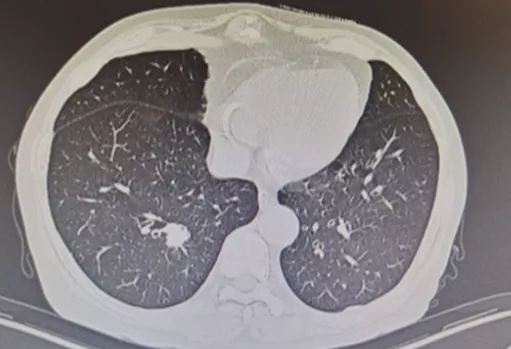

PET-CT

PET-CT对肺结节有一定作用,不同大小、不同类型的肺结节,有不同的诊断价值。但对于纯GGO,PET-CT的诊断价值有限;而对于部分实性GGO,PET-CT有一定价值。指南仅推荐>8mm实性结节或实性成分>8mm且具有高危因素可行PET检查。